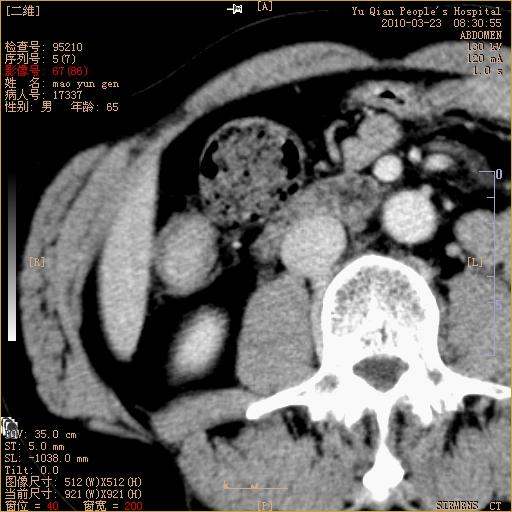

标题: CT25266:消瘦月余,前来肝部检查,请看看肠腔 [打印本页]

标题: CT25266:消瘦月余,前来肝部检查,请看看肠腔

升结肠肠壁增厚,不均强化,考虑升结肠腺癌可能性,建议肠镜检查。

1)考虑升结肠癌。2)右肾小囊肿。